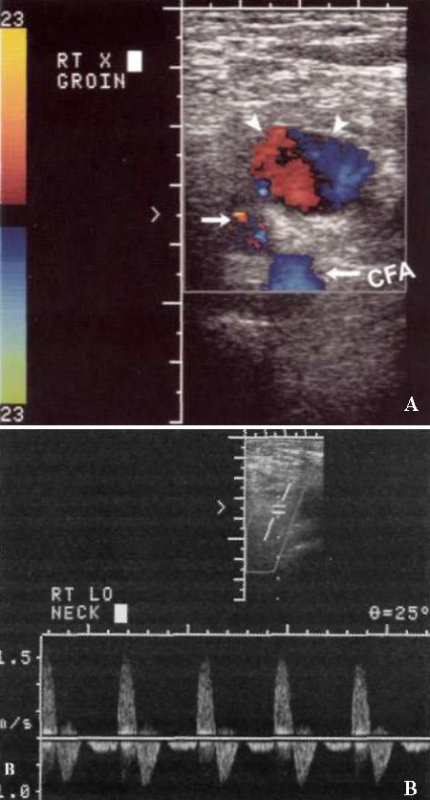

УЗИ: Ложная аневризма общей бедренной артерии

Фото 1. Ложная аневризма общей бедренной артерии. А – цветовая допплерограмма паховой области, выполненная в поперечной проекции: визуализируется общая бедренная артерия (CFA), стрелкой отмечена шейка аневризмы, указателями отмечена ложная аневризма, локализованная спереди, в которой наблюдается типичная картина «инь-янь» красного и синего цвета, что обусловлено завихрением кровотока. В – спектральная допплерограмма шейки ложной аневризмы подтверждает кровоток в обе стороны («туда-сюда»).